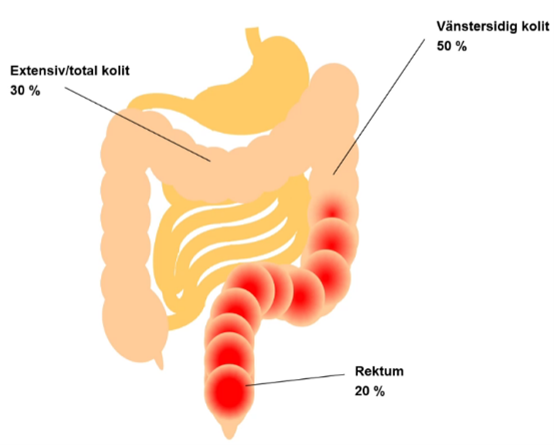

Ulcerös kolit, geografi och utbredning?

- Börjar distalt i rektum och breder ut sig proximalt

- Endast kolon

- Mukosal inflammation (bara slemhinna)

- Kontinuerlig inflammation

- Vänstersidig kolit (rektum, sigmoideum och vänster flexur)

- Rektum

- Bortom vänster flexur – extensiv/total kolit